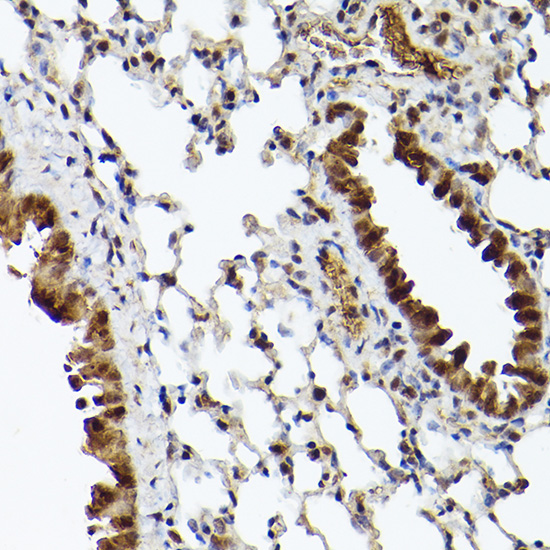

Immunohistochemistry of paraffin-embedded mouse lung using UBQLN4 Rabbit pAb.